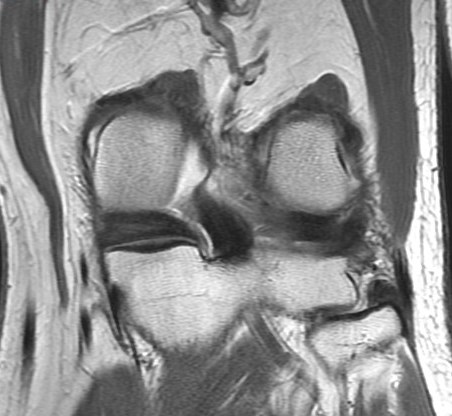

72 y/o M with all over knee pain. No known trauma. R/O meniscus tear.

Root attachment tear of the posterior horn of the lateral meniscus (RID2763)

Much more common to see these medially. These can be mimicked by magic angle but magic angle alone wont result in the irregularity seen here. Also there is some peripheral subluxation of the meniscus suggesting instability. Lateral root tears commonly occur with knee ligament sprains and tears. This patient had a chronic partial tear of the ACL (not shown) Reference article.